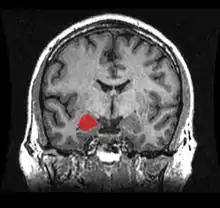

Frontal and side view of amygdala

Amygdala along with other subcortical regions, in glass brain.

Dorsal view of the amygdala in an average human brain

Frontal view of the amygdala in an average human brain